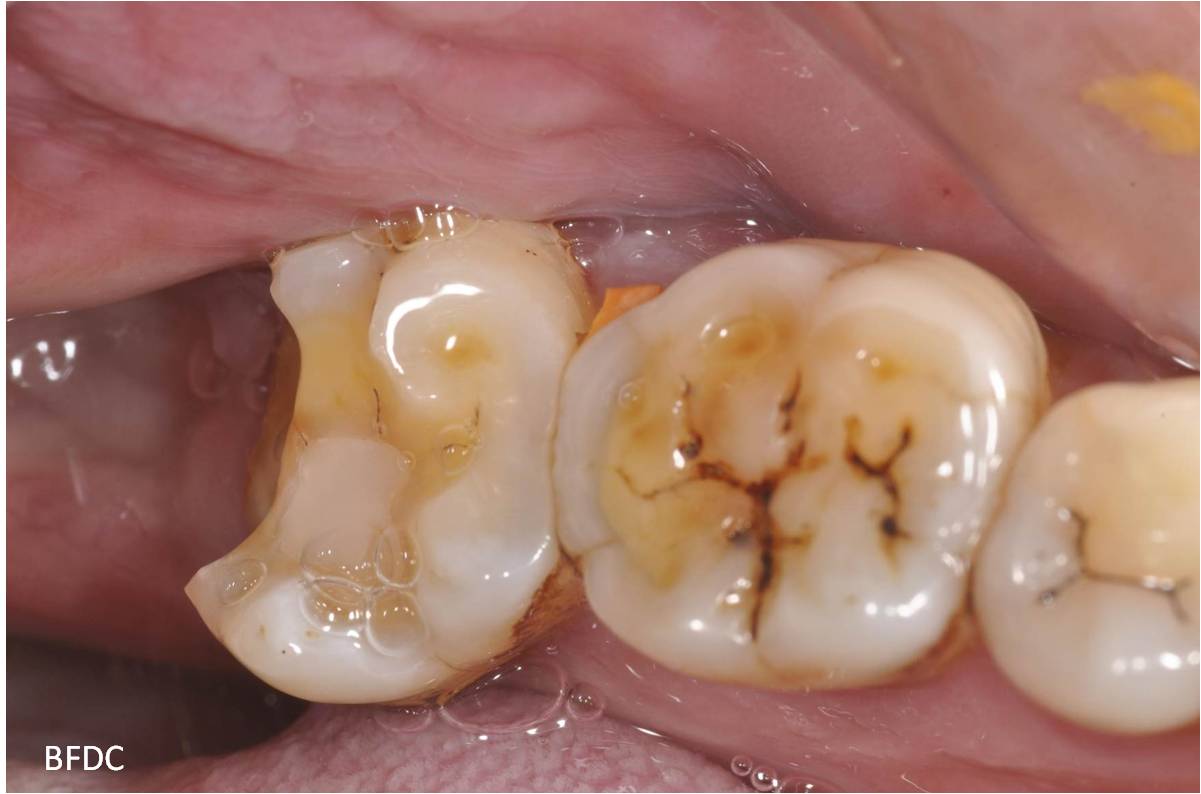

治療前,因智齒蛀牙,容易卡食物

蛀牙已至牙髓,建議先拔除智齒